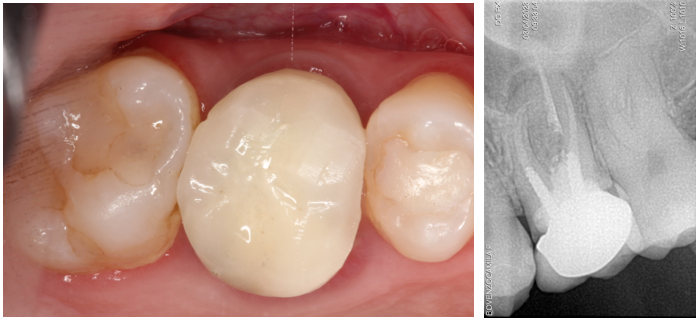

Paciente C.B.F.J., 33 anos, leucoderma, não-fumante e em boas condições de saúde sistêmica, relatou sensibilidade dolorosa durante mastigação no elemento 26, que já possuía tratamento endodôntico, pinos metálicos intrarradiculares e coroa metalocerâmica (Figura 1). Foi solicitada tomografia computadorizada de feixe cônico, na qual a imagem sugeriu fratura radicular na região da furca, descontinuidade óssea da cortical de seio maxilar e opacificação parcial do seio maxilar esquerdo (Figura 2). Foi realizada a exodontia e pôde-se confirmar a comunicação oroantral (Figura 3). Após curetagem do alvéolo, sem preocupação em curetar e remover a lesão cística sinusal, uma barreira reabsorvível foi recortada e posicionada no fundo do alvéolo para obliterar a descontinuidade óssea e impedir que células de tecido mole oriundas da cavidade sinusal invadissem a região alveolar (Figura 4). O alvéolo foi preenchido totalmente por coágulo sanguíneo do paciente (Figura 5) e o alvéolo foi selado por uma barreira não-reabsorvível (Figura 6), impedindo a invasão de fibroblastos do tecido gengival para dentro do alvéolo. Após duas semanas, a barreira estava estável e, então, foi removida, desnudando um tecido de granulação osteoblastogênico (Figura 7).